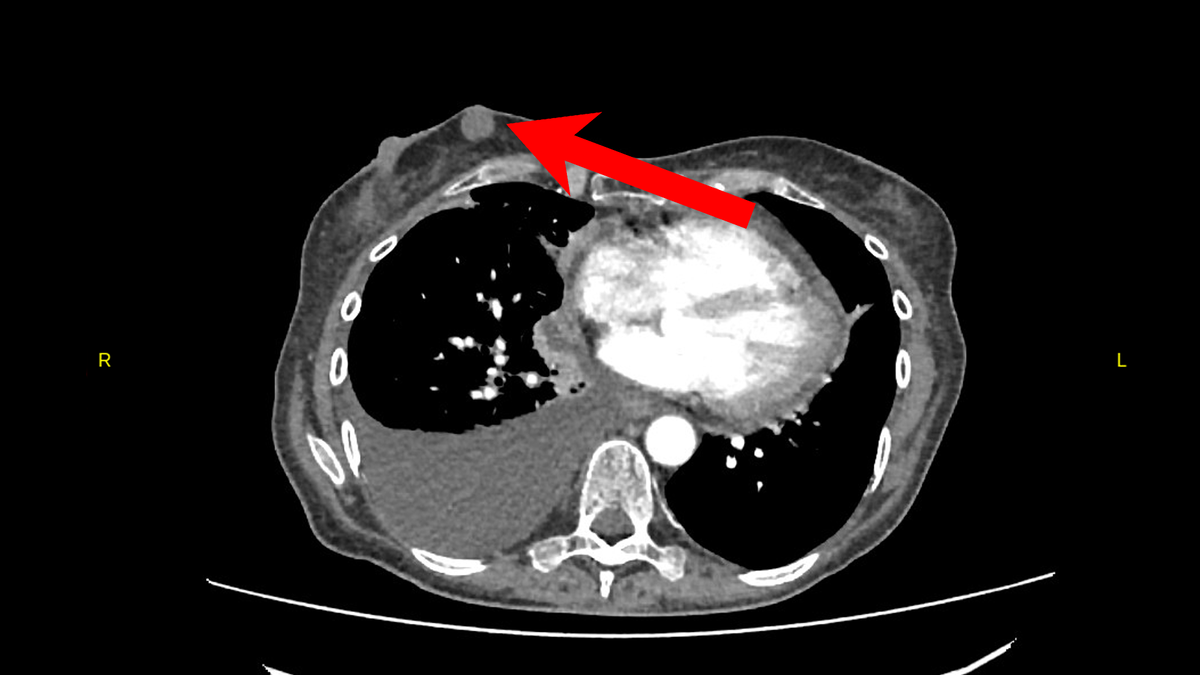

Пациентке было проведено КТ органов грудной клетки, брюшной полости и малого таза, которое открыло нам тайну этого клинического случая. Была выявлена массивная опухоль легкого с метастазами.

... в верхней доле правого легкого определяется патологическое образование 103х77мм... образование сливается с конгломератами увеличенных паратрахеальных лимфоузлов и прорастает: -в стенку трахеи, правый главный бронх и все долевые бронхи...

Опухоль легкого